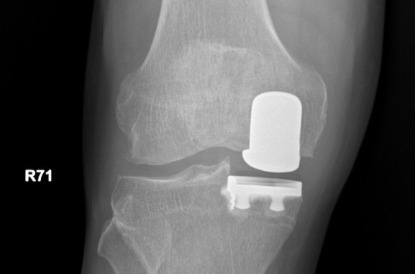

半膝人工關節置換術術後X光(膝蓋正面)